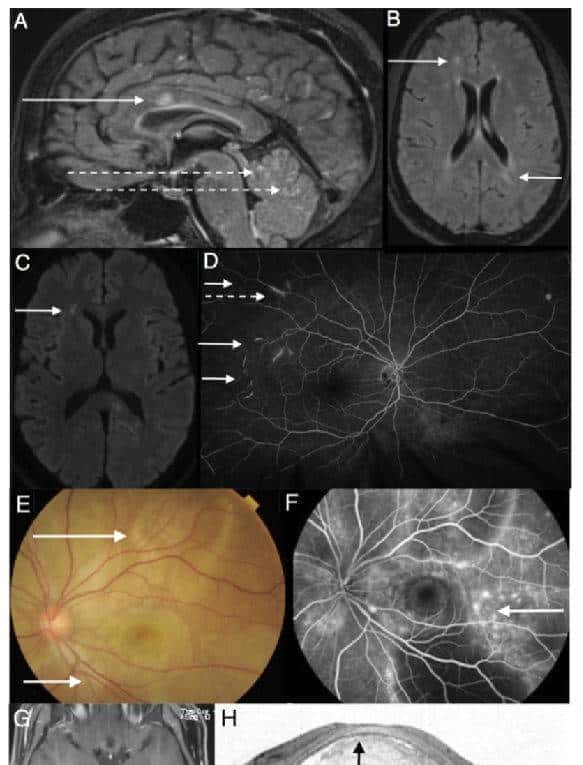

图1 Susac综合征(A-D)和VHK(E-H)

(A)Susac综合征患者矢状位FLAIR像上可见灰质和皮质下白质内的点状高信号,胼胝体经典“雪球”病变(实线箭头)。在胼胝体内部也可以看到“辐射条状”病变。软脑膜不规则增强(虚线箭头)。(B)轴位FLAIR像上可见双侧大脑半球皮质下白质高信号(箭头);(C)轴位DWI像显示对应病灶处(箭头)高信号。(D)眼底荧光素血管造影(FFA)显示特征性视网膜分支动脉闭塞(实心箭头)和长片状小动脉壁荧光(虚线箭头)。(E)VHK患者眼底摄影可见急性期继发于视网膜下积液的多个视网膜浆液性分离(箭头);(F) FFA可见独特的“星空样”外观(箭头),与荧光素泄露有关,哪些配合脉络膜炎、视网膜色素上皮的水平和效果在视网膜下空间染色的积累方面,(G)头颅MRI可见小脑膜轻度增强; (H)光学相干断层扫描(OCT)显示视网膜下积液(箭头)。